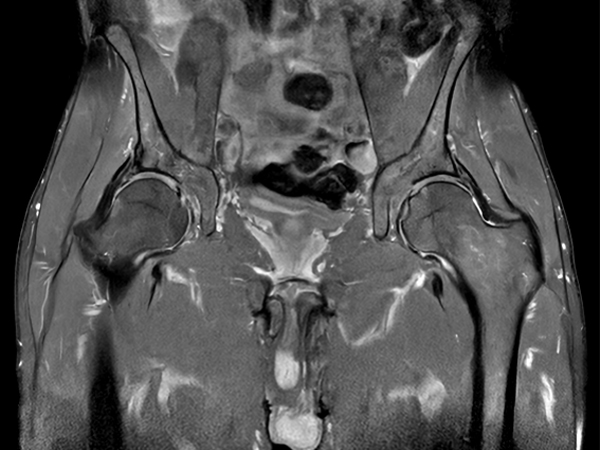

Fast bilateral hips, with SmartSpeed Precise

Fast bilateral hips_MR 5300_R11